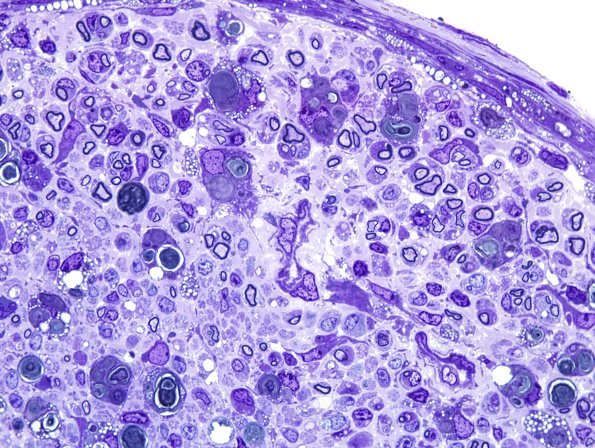

Washington University Experience | PERIPHERAL NEUROPATHY | 4 AXONAL DEGENERATION | 2 Plastic Sections | 11A5 Mouse sciatic (Case 11) Plastic 100X 4.jpg

This mouse nerve, in which constriction injury was induced experimentally, shows prominent axonal degeneration.